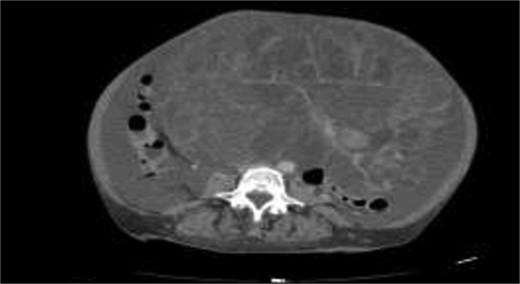

A 58-years-old female previously healthy, presented with gradual increase in the abdominal circumference and a massive weight loss of 17 kg over the past 6 months (Body Mass Index, BMI = 18). She had her menarche at 13 and her menopause at 41. The patient conceived one child without fertility or hormone therapy. Computed tomography (CT) showed an enormous abdominal tumor with minor peritoneal effusion, atelectasis, and pleurisy over the right lung (Figs 1 and 2).

The patient was scheduled for a diagnostic laparoscopy which revealed 3 L of ascites, no peritoneal carcinomatosis and a large polylobate partially cystic tumor arising from the pelvis. The mass was resected in one piece through xypho-pubic laparotomy. It weighted 9 kg (240 × 180 × 235 mm) and had relatively thick walls attached to the left ovary (Figs 3–5). A concomitant total hysterectomy, right adnexectomy, omentectomy, and appendectomy were performed with multiple biopsies from the Douglas, liver, omentum, mesenteric, peritoneal, and pelvic walls.